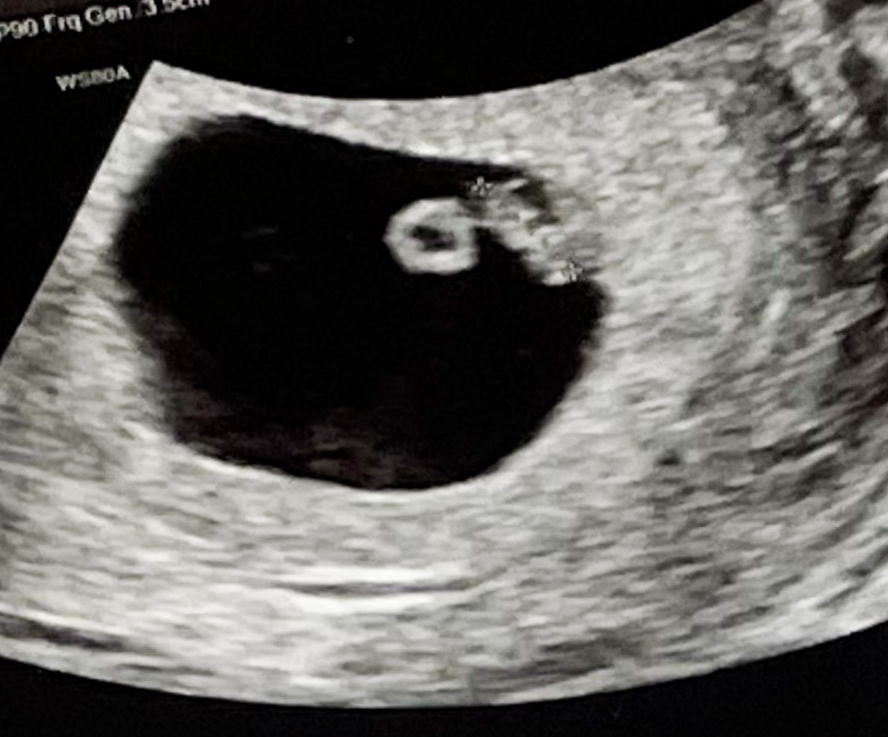

6주 4일

2주 전에는 아기집 밖에 안보였는데

이번에는 심장박동도 들을 수 있었다.

애기에 난황에 심장소리까지!!

2주동안 정말 많이 컸다.

동그라미가 머리인가 싶었는데

그게 난황이고 막대기가 애기라고 하셨다.

0.68 cm로 1 cm도 안된 아주쪼고미였다.

심장박동은 124bpm으로 아주 우렁찼다.

1cm도 안되는게 심장이 이렇게 우렁차다니 신기할 따름이었다.